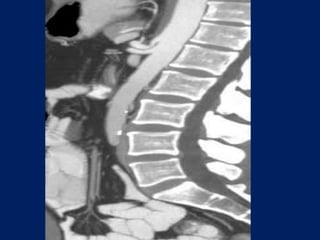

angulations and narrowing of the proximal celiac axis. Sagittal 3D image of a patient with epigastric pain

Sagittal (MIP) of a patient with recurrent abdominal pain reveals focal calcified plaque.